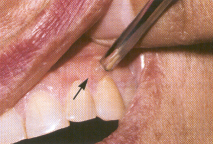

Fig. 9.22. Pénfigo vulgar. Formación

de una ampolla (flecha) sobre una encía de aspecto normal tras

presionar con un instrumento romo, que indica signo de Nikolsky positivo.

(Fig. 9.21). Tanto en la piel como en las mucosas, se presenta un signo

de Nikolsky positivo (desprendimiento del epitelio sano por frotación)

(Fig. 9.22).3 El diagnóstico clínico debe ser